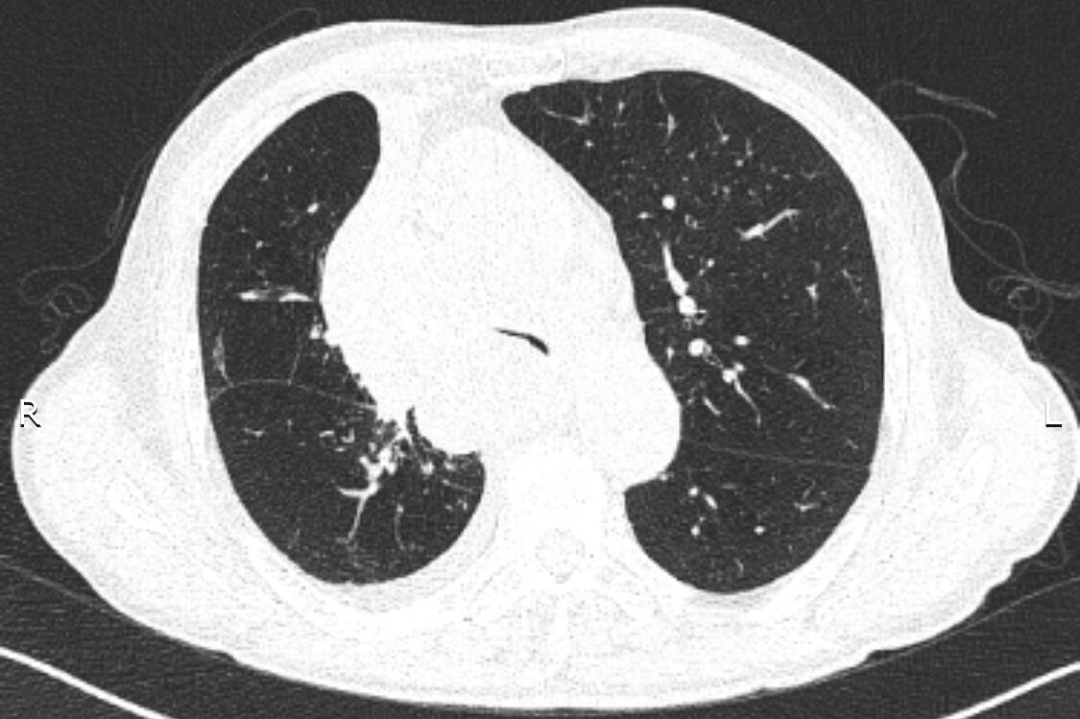

入院后給予吸氧、藥物治療,癥狀緩解不明顯。張強(qiáng)主任結(jié)合患者的癥狀、體征及CT表現(xiàn),考慮憋喘主要為腫瘤浸潤壓迫氣道引起,緊急行電子氣管鏡檢查,明確了氣道被壓迫情況。正常成人氣管內(nèi)鏡約2.5cm,患者氣管下段重度狹窄,直徑僅約3mm,而且狹窄一直延續(xù)到右主支氣管末端,左主支氣管狹窄情況還稍輕些。建議患者可緊急置入支氣管支架短期緩解癥狀,綜合支架特點(diǎn)、支架定制周期、患者病情、費(fèi)用等情況后,家屬希望能為患者盡快放置硅酮支架。張強(qiáng)主任立即聯(lián)系醫(yī)務(wù)科,并聯(lián)系支架置入經(jīng)驗(yàn)豐富的外請專家王曉東教授前來指導(dǎo),為患者保駕護(hù)航。

支架放置前:CT提示近圓形的氣管被壓迫至“一條縫”